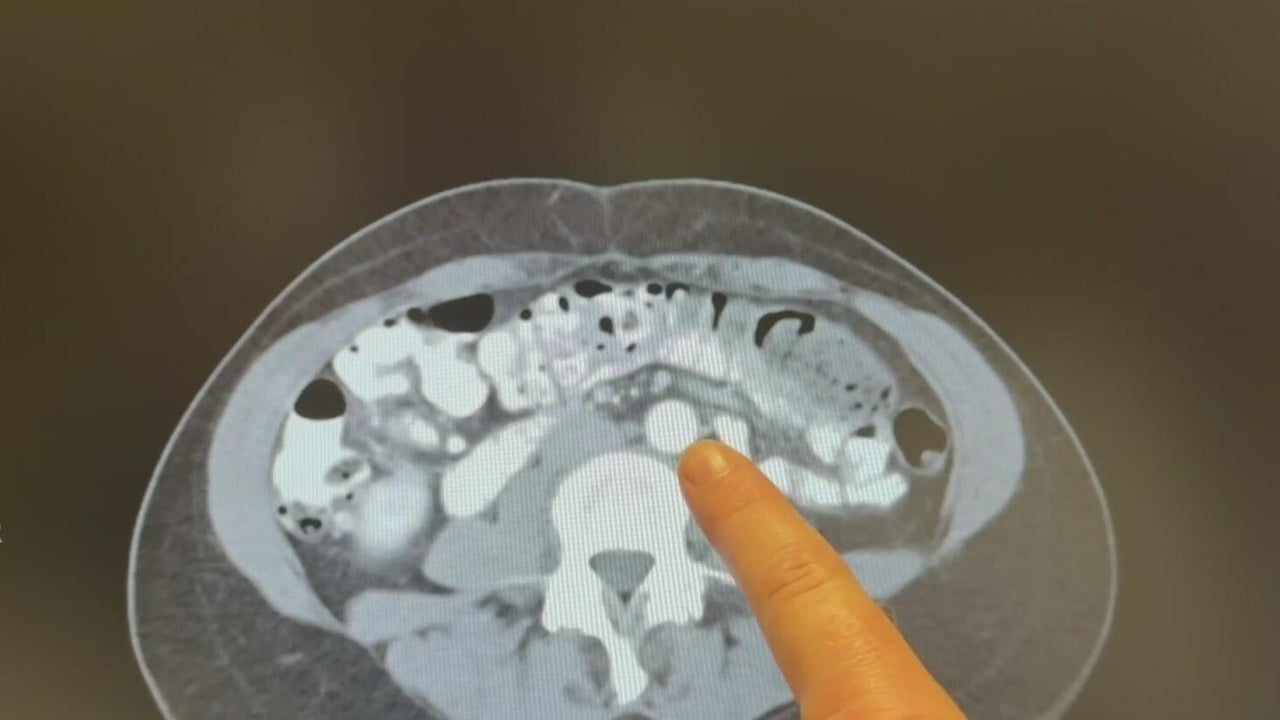

September is Gynecologic Cancer Awareness Month

Doctors say one kind of cancer is on the rise.